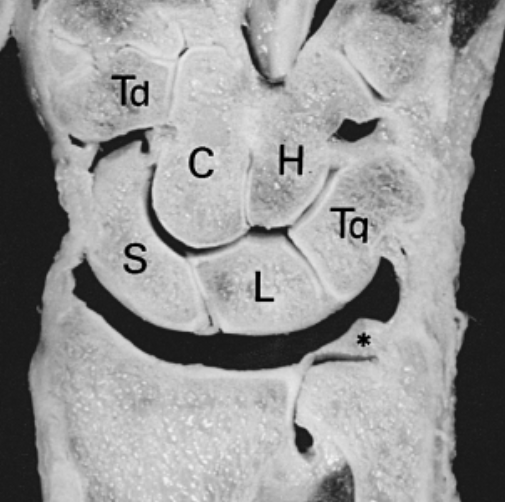

Het bandje tussen scaphoid (S) en lunatum (L) kan inscheuren bij hier op inwerkende krachten.

Bij letsel van het bandje wordt de samenhang van de handwortel doorbroken en gaan scaphoid en lunatum onafhankelijk van elkaar bewegen. Hierdoor kan artrose ontstaan.